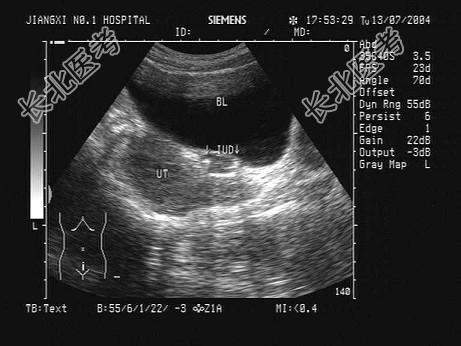

- 患者,女性, 40岁,妇科超声检查如图,